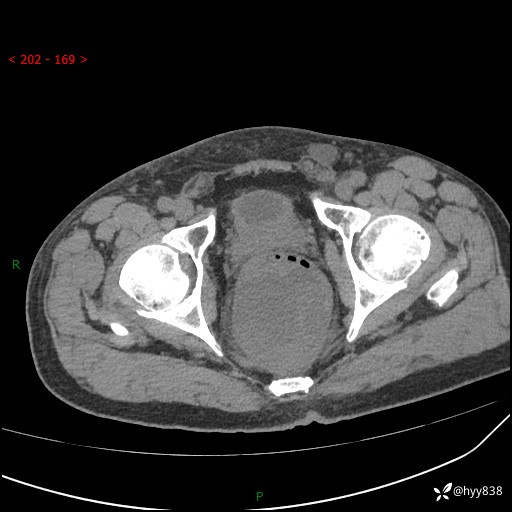

盆腔CT平扫+增强